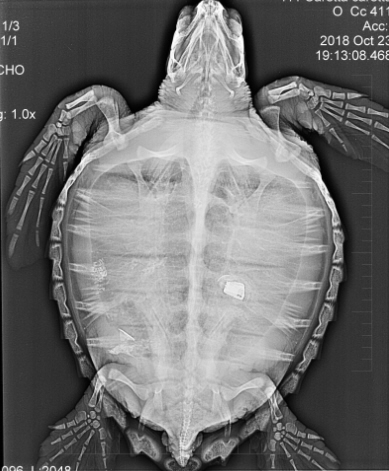

Dyrlægerne hos akvariet gjorde store øjne, da de gav skildpadden en ultralydsscanning og så, hvad der lå og rumsterede i dens tarm.

Det lille dyr havde nemlig gumlet et stykke af en lighter i sig, og det kom der et noget spøjst røntgenfotografi ud af:

Ikke ligefrem et typisk røntgenbillede

Nederst i billedet kan man se det lille stykke lighter, som drillede padden